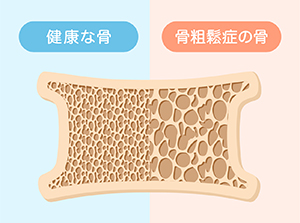

体の老化はお口の老化から始まります。

体の老化はお口の老化から始まります。